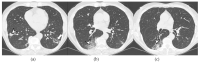

Polymyositis and dermatomyositis are autoimmune idiopathic systemic inflammatory diseases, characterized by various degrees of muscle inflammation and typical cutaneous lesions-the latter found in dermatomyositis. The underlying pathogenesis is characterized by a high level of uncertainty, and recent studies suggest diseases may have different immunopathological mechanisms. In polymyositis, components of the cellular immune system are involved, whereas in dermatomyositis, the pathogenesis is mainly mediated by the humoral immune response. The interstitial lung disease occurs in one-third of polymyositis and dermatomyositis patients associated with worse outcomes, showing an estimated excess mortality rate of around 40%. Lung involvement may also appear, such as a complication of muscle weakness, mainly represented by aspiration pneumonia or respiratory insufficiency. The clinical picture is characterized, in most cases, by progressive dyspnea and non-productive cough. In some cases, hemoptysis and chest pain are found. Onset can be acute, sub-acute, or chronic. Pulmonary involvement could be assessed by High Resolution Computed Tomography (HRCT), which may identify early manifestations of diseases. Moreover, Computed Tomography (CT) appearances can be highly variable depending on the positivity of myositis-specific autoantibodies. The most common pathological patterns include fibrotic and cellular nonspecific interstitial pneumonia or organizing pneumonia; major findings observed on HRCT images are represented by consolidations, ground-glass opacities, and reticulations. Other findings include honeycombing, subpleural bands, and traction bronchiectasis. In patients having Anti-ARS Abs, HRCT features may develop with consolidations, ground glass opacities (GGOs), and reticular opacities in the peripheral portions; nonspecific interstitial pneumonia or nonspecific interstitial pneumonia mixed with organizing pneumonia have been reported as the most frequently encountered patterns. In patients with anti-MDA5 Abs, mixed or unclassifiable patterns are frequently observed at imaging. HRCT is a sensitive method that allows one not only to identify disease, but also to monitor the effectiveness of treatment and detect disease progression and/or complications; however, radiological findings are not specific. Therefore, aim of this pictorial essay is to describe clinical and radiological features of interstitial lung diseases associated with polymyositis and dermatomyositis, emphasizing the concept that gold standard for diagnosis and classification-should be based on a multidisciplinary approach.